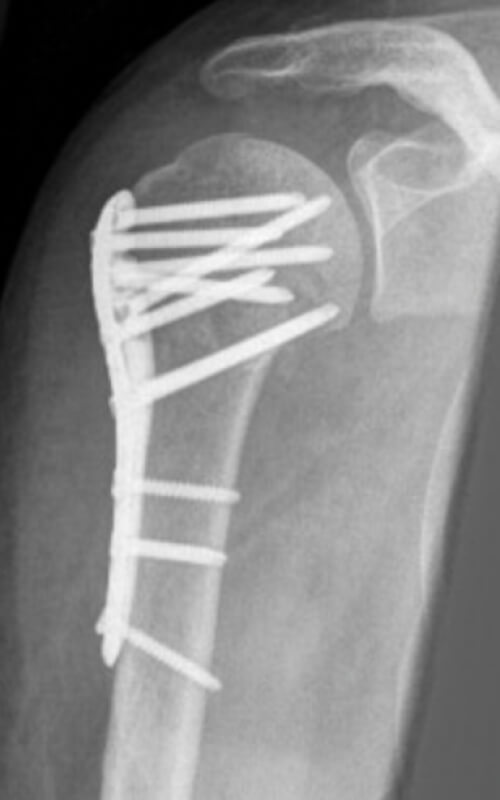

L’osteosintesi è l’intervento chirurgico, eseguito a cielo aperto, che permette di riallineare e fissare i frammenti ossei dovuti a una frattura. Tanto nel caso dell’omero prossimale, quando nel caso della clavicola, se la frattura è scomposta si procede quindi con questa pratica chirurgica, durante la quale le parti ossee vengono riposizionate e fissate tramite placche e viti o chiodo endomidollare.